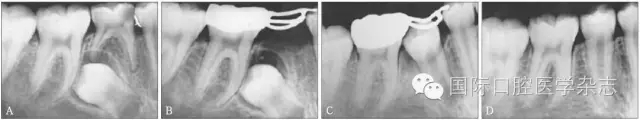

圖3為一因“乳磨牙爛牙”前來就診兒童的X線片檢查。影像學(xué)檢查顯示:第二乳磨牙近中深齲,近遠中牙根吸收均不明顯,但遠中根尖病變引起了第二前磨牙萌出方向的改變。臨床處置:及時拔除了齲壞的第二乳磨牙,制作第一恒磨牙帶環(huán)絲圈間隙維持器,3個月后復(fù)診,X線片顯示第二前磨牙萌出方向逐漸正向調(diào)整;6個月后復(fù)診,第二前磨牙基本正位萌出;1年后復(fù)診,第二前磨牙調(diào)整到位。從圖3的病例可以看出:乳磨牙根尖周病變會引起恒牙萌出方向的改變,出現(xiàn)咬合紊亂的潛在性表現(xiàn),但臨床上通過去除病灶牙與簡單的間隙維持、未實施牽引助萌即糾正了該病例潛在性的咬合紊亂發(fā)生。

A:下頜第二乳磨牙近中齲,X線片顯示遠中根尖周病變引起繼承恒牙萌出方向改變;B:擬及時拔除病變的下頜第二乳磨牙,行間隙維持;C:拔除病變的下頜第二乳磨牙間隙維持后一段時間,繼承恒牙萌出方向發(fā)生正向改變;D:繼承恒牙正位萌出。

圖3 乳牙根尖炎癥引起繼承恒牙萌出方向改變的典型病例

Fig 3 Typical case oferuptive direction change caused by periapical infection of primary tooth